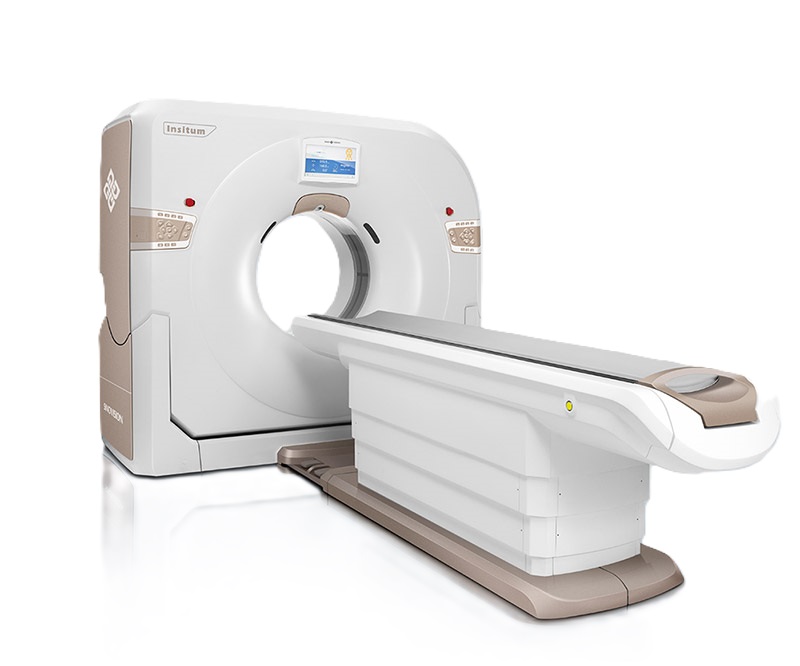

128-срезовый компьютерный томограф SinoVision InsitumCT 568

Инновационный 128-срезовый компьютерный томограф SinoVision InsitumCT 568 – это сочетание высокой скорости работы, низкой дозы и максимума возможностей для подавляющего большинства клинических случаев, как в рутинных, так и в углубленных специализированных исследованиях, в том числе педиатрические и кардиологические исследования при сверхнизких дозах.

РМК

Полнофункциональный 128-резовый компьютерный томограф InsitumCT 568 - это лучшее в новом поколении широкодиапазонных томографов с 128 срезами и большой диафрагмой. Этот КТ-сканер с большой апертурой обеспечивает 128 срезов КТ с диафрагмой 76 см, улучшает разрешение изображения до 21Lp/cm, помогает точно диагностировать и лечить заболевания, а также значительно улучшает клинические характеристики и расширяемость оборудования. Позволяет реализовать визуализацию в высоком разрешении и в малых дозах лучевой нагрузки.

Полнофункциональная платформа клинической диагностики может точно определять местонахождение и диагностировать общие повреждения качественно и количественно, а также достигать полнофункциональных клинических показателей, включая обширные кардиологические исследования со сверхнизкими дозами лучевой нагрузки.

Гентри

- Апертура: 76 см

- Наклон: 30 градусов

- Поле зрения: 50 см

Стол пациента

- Ширина стола: 42 см

- Максимальная нагрузка: 250 кг

- Перемещение по горизонтали: 1950 мм

- Скорость перемещения: 5 мм в секунду

- Высота стола в самом низком положении: 425 мм

- Подъем по вертикали: 565 мм

- Особенности: Управление с пульта, аксессуары для фиксации и укладки